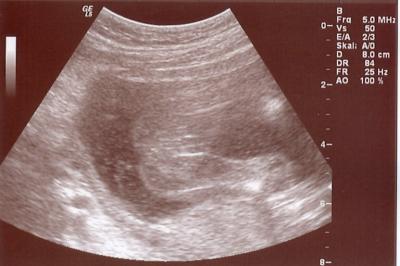

Also Mädels, bei dawn konnt ich leider nix erkennen, bei lililevi schon eher. Ich pack mal ein Bild anbei und frag Euch mal: Junge oder Mädchen? LG Wuschel

Bild zu nochmal wegen Outing-Bild - kleine Umfrage :-) - Forum für November - Mamis

Ja das ist der Popo und die Schenkel von unten. Dazwischen ist das Geschlecht (welches auch immer?) *kopfkratz*

Ahhhhh, jetzt ... habs sogar ich gerafft wies liegt. Mir gings wie bei so nem optischen Täuschungbsild ... man muss lang draufschauen und sich was anderes vorstellen um was zu erkennen .... Also, eine Freundin hat mir erklärt, dass das, wenn man drei weiße Linien sieht, das eindeutige Zeichen für ein Mädchen ist und das ist bei dir der Fall finde ich ... sie hat mir das Bild von ihrer Tochter gezeigt und das sah genauso aus. Liebe Grüße nochmal, von der, dies jetzt doch gerafft hat.

Mädchen so sah es damals bei Julia auch aus